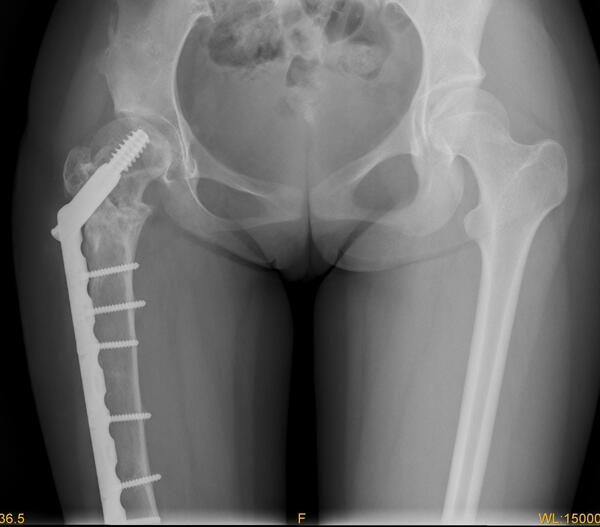

图1女性,18岁,术前肢体短缩9cm图2 术后力线纠正

图3 术后肢体等长